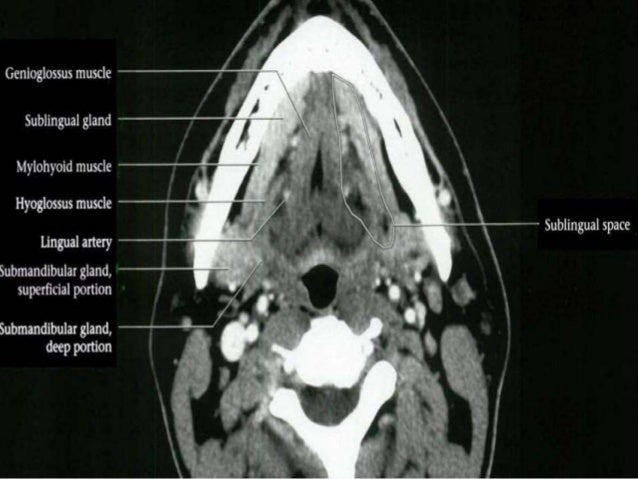

mylohyoid digastric submandibular gland sublingual

cavity pharynx mylohyoid

neck anatomy